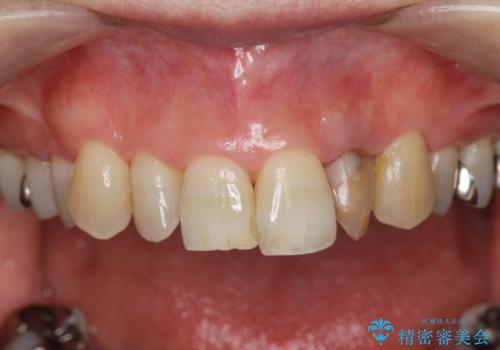

- 目立つ前歯の著しい変色の改善を求めて来院されました。

根管治療が為されたまま、クラウンの装着が行われず変色し審美障害を来している状態です。